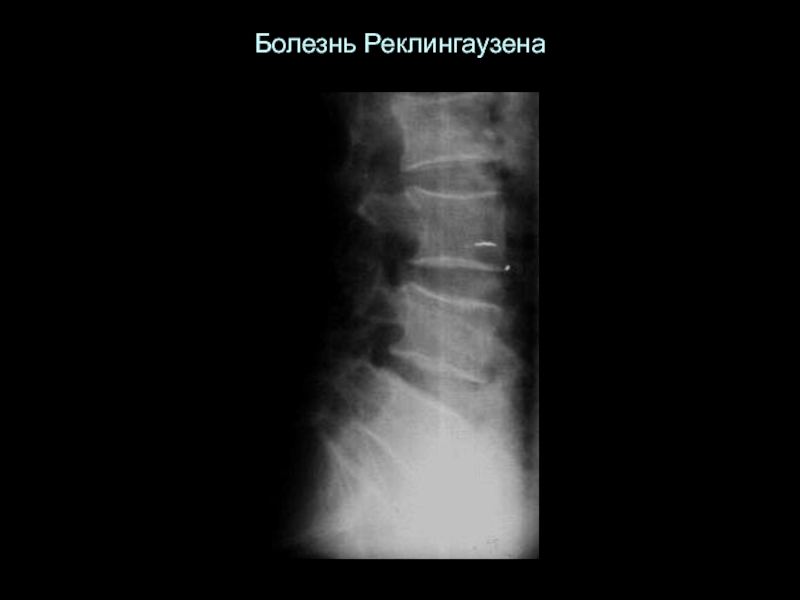

Слайд 10Болезнь Реклингаузена

Болезнь Реклингаузена